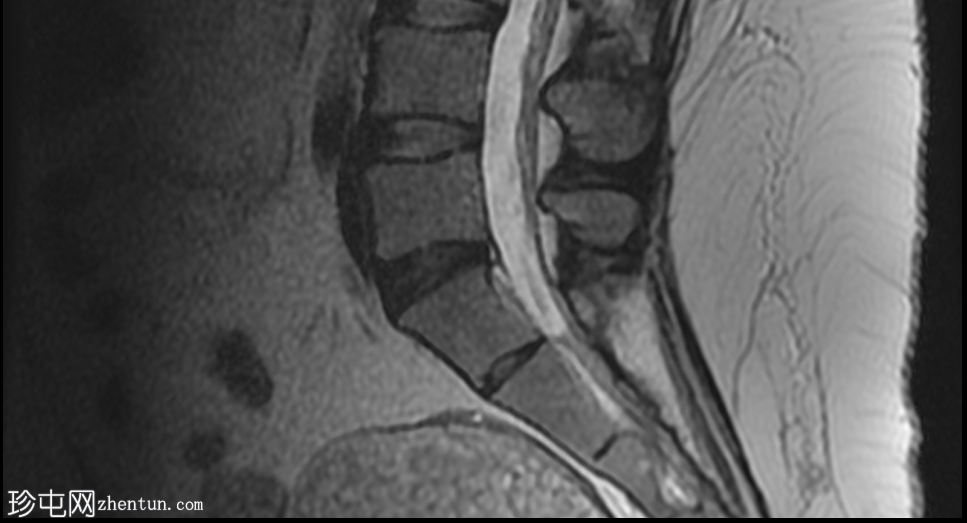

MRI

矢状位

T2加权像

盆腔可见部分囊性肿块,内含脂肪球。